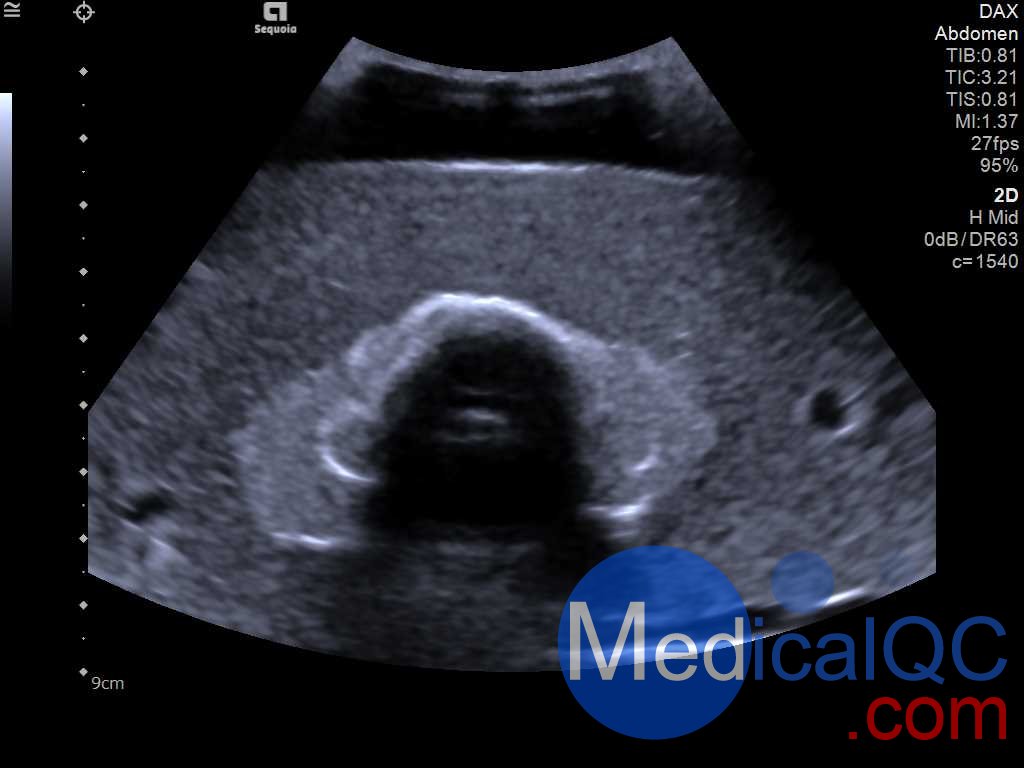

Cirs074甲狀腺超聲訓(xùn)練模體,Cirs074甲狀腺穿刺模體超聲成像圖:

Cirs074甲狀腺超聲訓(xùn)練模體,Cirs074甲狀腺穿刺模體超聲成像圖